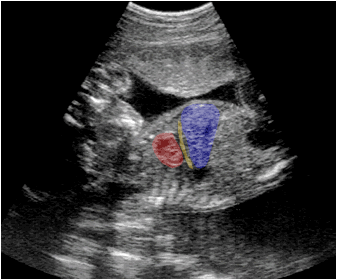

Ecografía fetal que muestra en un corte longitudinal el corazón (rojo), el hígado (azul) y entre ambos una zona econegativa que representa al diafragma (amarillo).